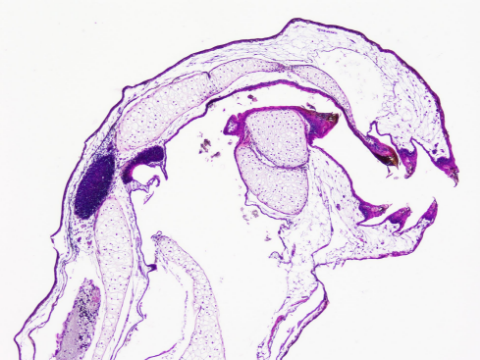

病理組織片切片標本

ウィルス感染や寄生虫に侵された組織切片標本の作製をおこないます。餌料の違いによる体細胞の変化調査、冷凍による肉質変化調査などのための標本作製依頼にも対応しております。